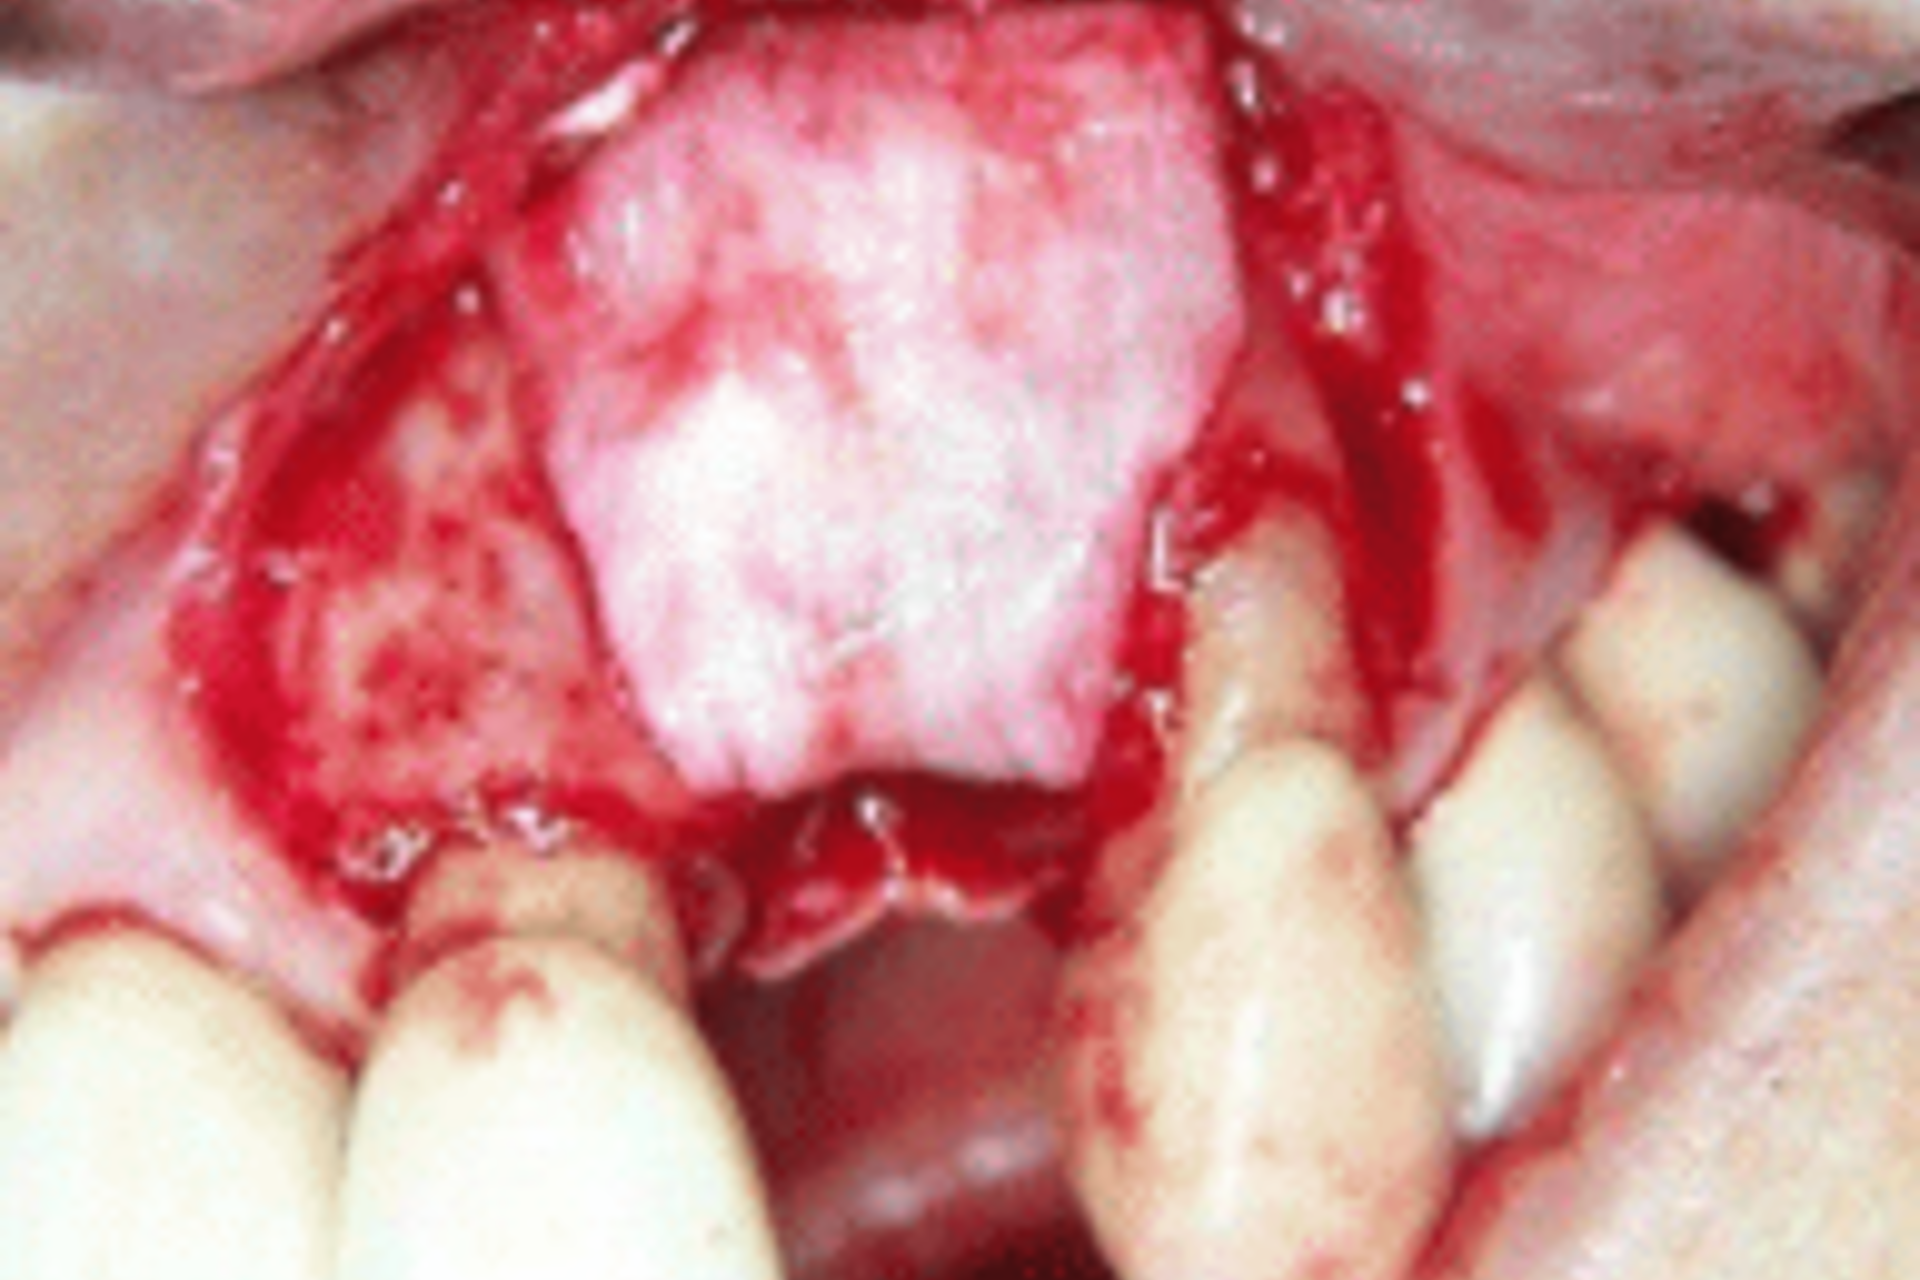

Bone regeneration around dental implants is achieved by grafting bone. Most commonly bone grafting is required when a patient does not have enough healthy natural bone at the dental implant site to support a dental implant. (Figures 15 A, B & C).

Figure 15C below, shows the graft now covered by membrane.